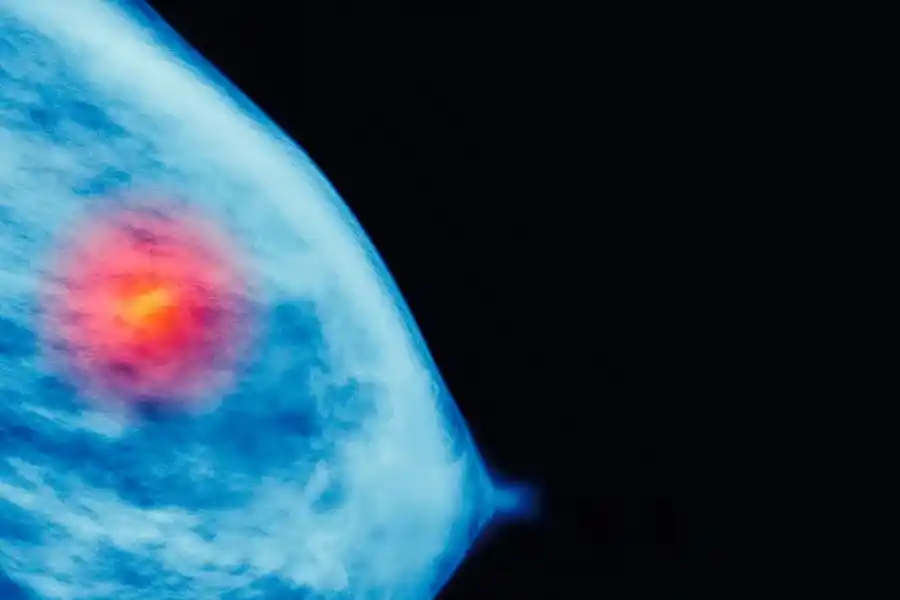

“Es muy importante que la mujer aprenda a conocer sus mamas, como lo es estar atentas a la aparición de nódulos, derrames de sangre por pezón, retracción de la piel o cualquier otro signo fuera de lo común -sostuviAlba Posse-. Pero no es el autoexamen mamario el diagnóstico precoz por excelencia. Las lesiones palpables suelen tener al menos un centímetro de diámetro, el beneficio de los estudios de screening o tamizaje como la mamografía es detectar estos tumores en etapa subclínica, siendo la posibilidad de curación más alta. En caso de aparición inesperada de un nódulo palpable, es importante no perder la calma y recurrir al profesional para su estudio y control”.